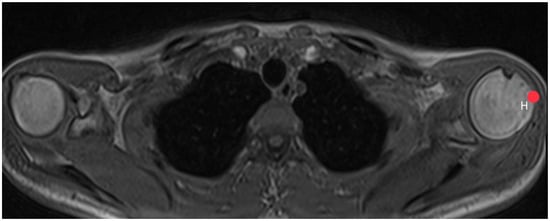

2.3. Acromion Index (Figure 1)